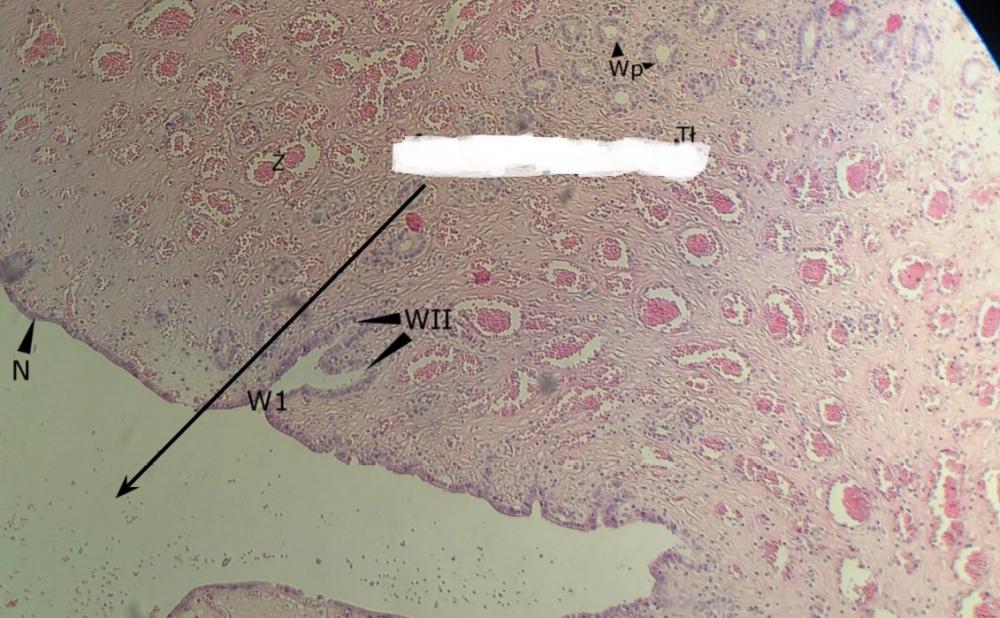

Pytanie 495

nabłonek jednowarstwowy walcowaty (jajowód)

Pytanie 496

splot żylny (jajowód)

Pytanie 497

światło jajowodu (jajowód)

Pytanie 498

wpuklenia błony śluzowej (jajowód)

Pytanie 499

wpuklenia błony śluzowej jajowodu (jajnik, rdzeń)